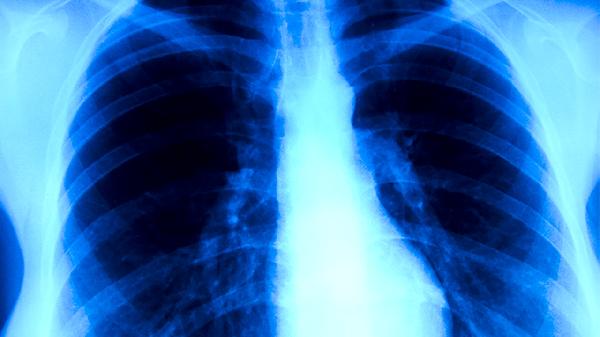

肺结核可通过中医辨证施治结合抗结核药物实现临床治愈,关键环节包括扶正祛邪、调理肺脾、清热解毒、活血化瘀、固本培元。

中医认为肺结核属"肺痨",正气不足时痨虫乘虚而入。治疗需用黄芪、党参等补益肺气,配伍百部、白及杀痨虫。临床常用百合固金汤加减,配合异烟肼等西药抑制结核杆菌,双管齐下提升疗效。

结核病灶局部炎性反应属热毒蕴结。黄芩、鱼腥草等清热解毒药能减轻肺部炎症,与利福平联用可降低耐药性风险。验方结核散含夏枯草、猫爪草等,对空洞型肺结核效果显著。

治疗期间宜食山药粥、银耳羹等润肺健脾膳食,避免辛辣燥热食物。太极拳八段锦等柔缓运动有助于恢复肺功能,但需避免剧烈运动耗气。保持居室通风干燥,每日艾灸足三里、肺俞穴各10分钟可巩固疗效。康复后每季度复查胸片,连续两年未复发视为临床治愈。需注意中医药起辅助作用,规范抗结核化疗仍是根治关键,任何治疗方案都应在专科医师指导下进行。